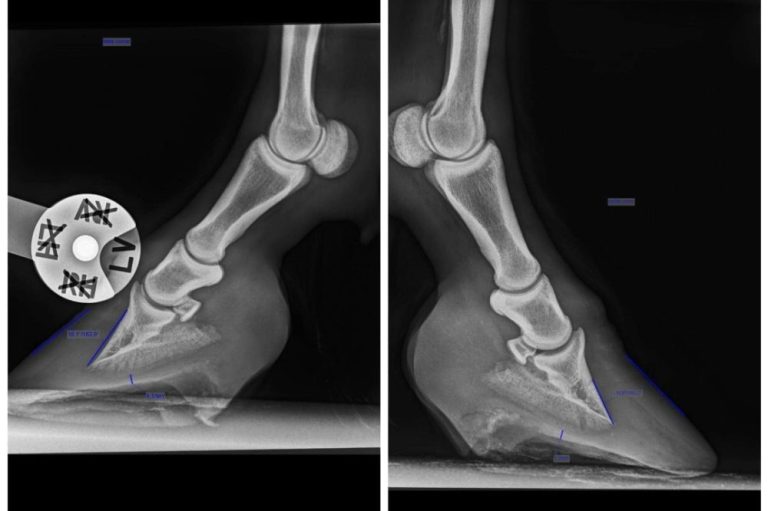

Huforthopädie

Fachgerechte Hufbearbeitung zur Verbesserung der Hufgesundheit mit Laufkomfort und Leistungsfähigkeit Deines Pferdes.

Umfassende Diagnostik und Behandlung von Hufkrankheiten und Problemen.

Eigene Forschung an Tothufen, um die Hufsituation am Pferd besser beurteilen und positiv beeinflussen zu können.